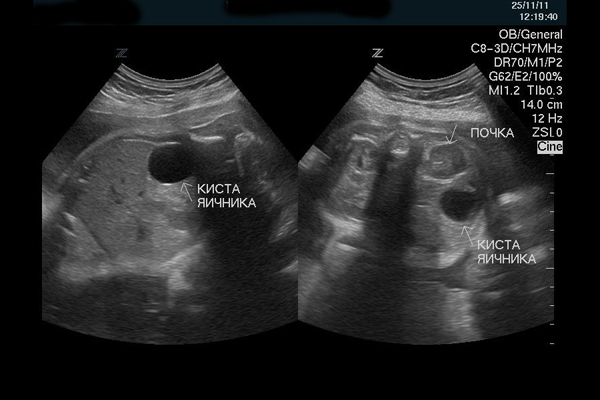

Как выглядит киста на УЗИ

Кистозное образование (простое) выглядит как анэхогенная полость, имеющая тонкие стенки, усиление эхо-сигнала четко прослеживается. Плотного содержимого в простой кисте нет, кровотока тоже.

На фото ниже продемонстрировано УЗИ кисты яичника.